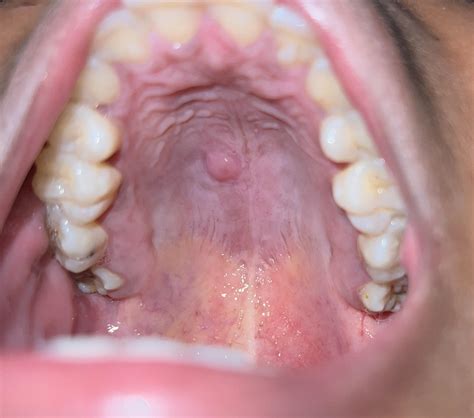

Discover the common causes of a nodule in roof of mouth. Learn when a hard bump or oral lesion requires professional dental evaluation. Understand potential triggers like palatal tori, cysts, or oral infections, and identify symptoms that warrant a visit to your dentist for a proper diagnosis and effective treatment plan for your oral health.

Read full article: Nodule In Roof Of Mouth